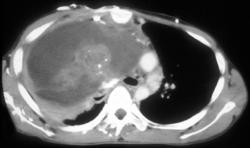

Germ Cell Tumor Invades the Chest Wall